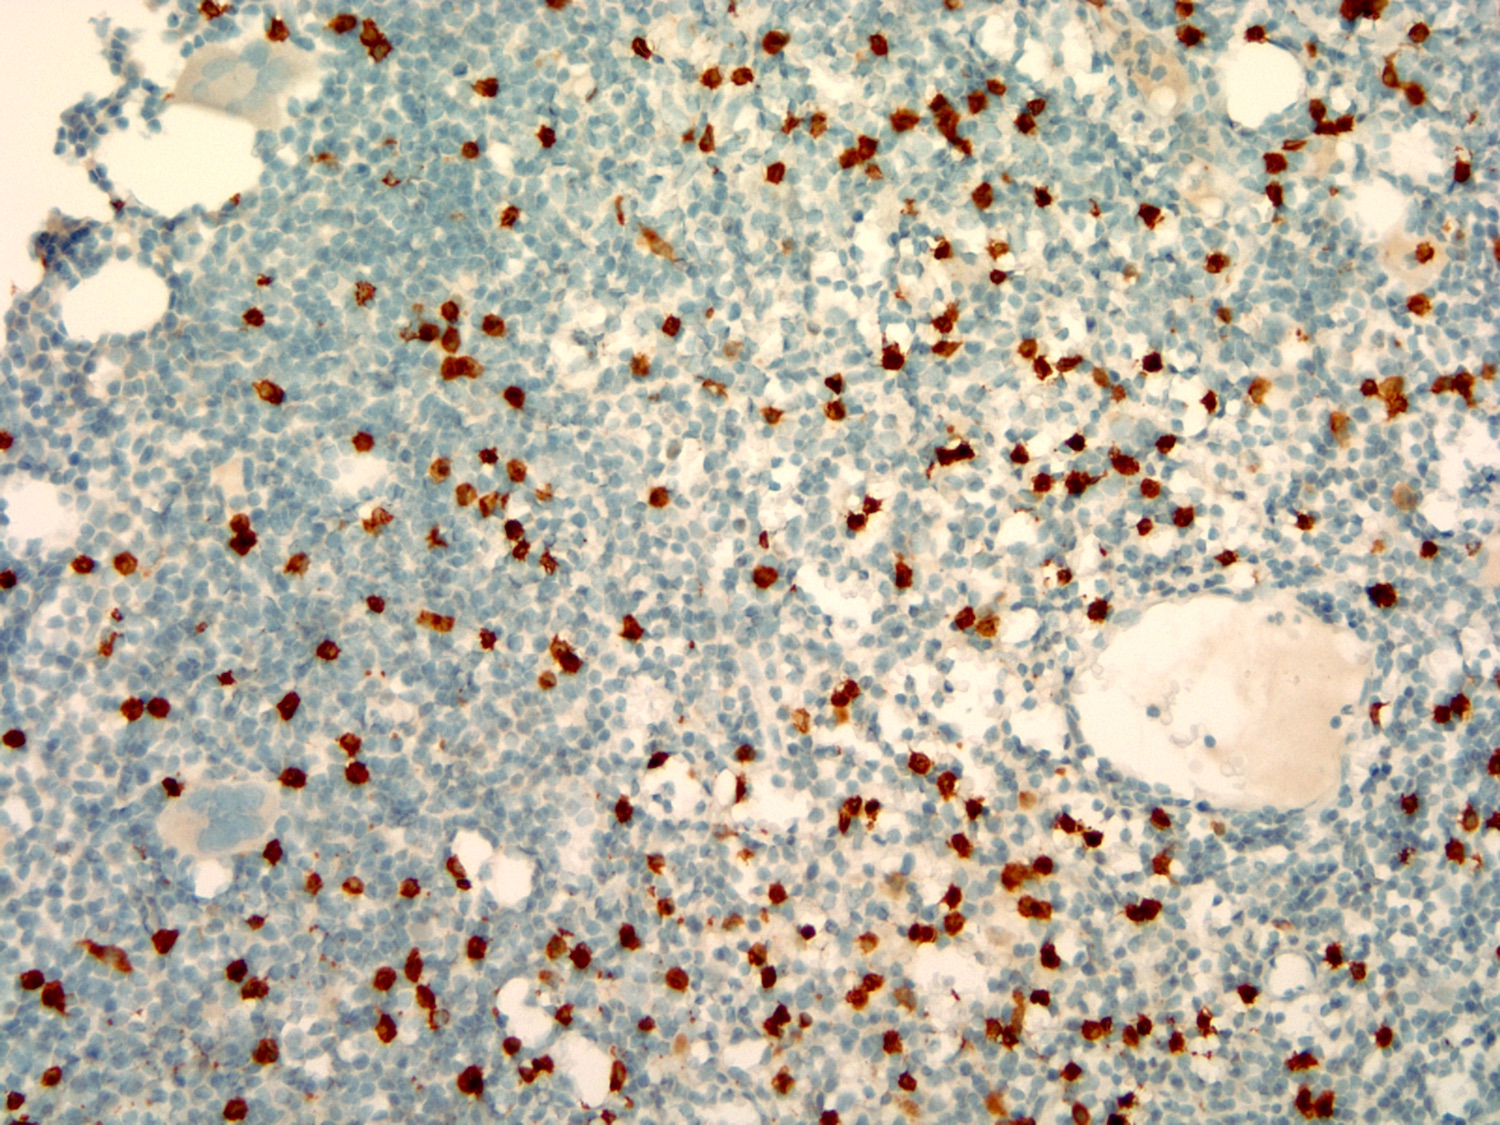

Microscopic (histologic) images

Contributed by Ling Zhang, M.D.

Positive stains

- Immunohistochemical study: Immunohistochemical stains and in situ hybridization stains are performed on the core biopsy with adequate controls. CD20 and PAX5 highlight a diffuse infiltration of neoplastic B cells, occupying 80% of total cellularity. CD3 highlights scattered interstitial T lymphocytes, ranging from 2% to 5%. CD138 highlights scattered plasma cells, focally forming small clusters, accounting for approximately 5% of the total cells. By in situ hybridization (ISH), the plasma cells are positive for kappa light chain and negative for lambda light chain.